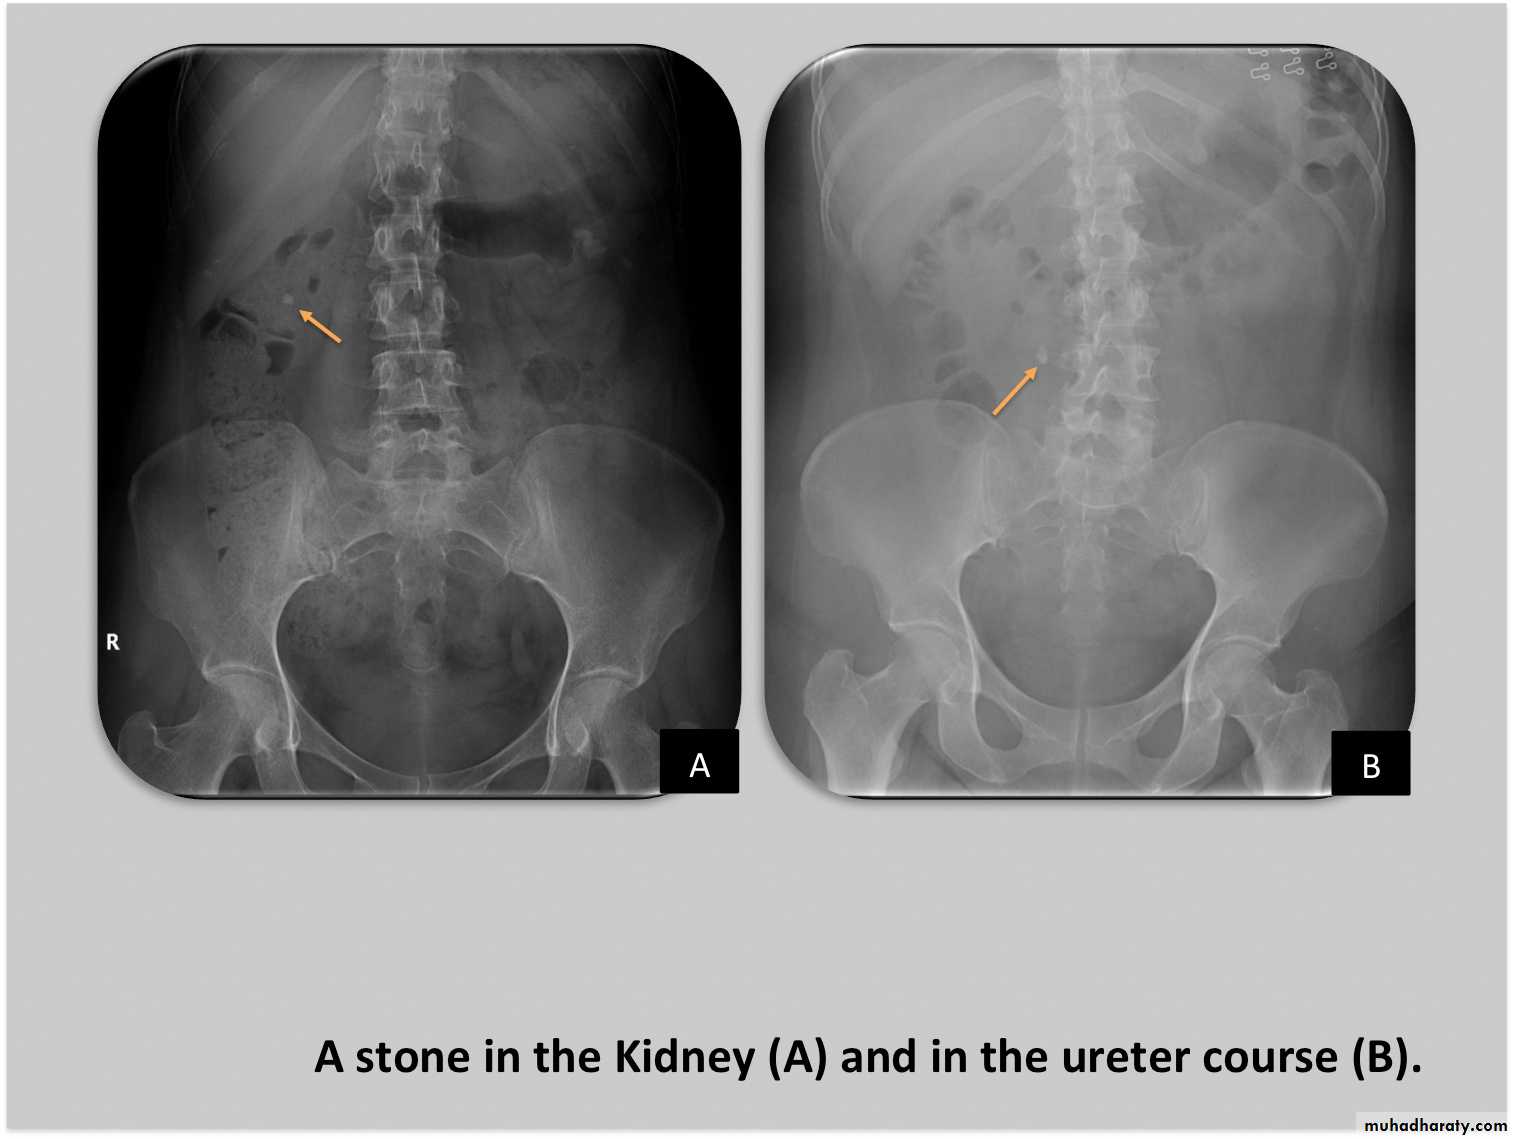

Renal stones

High density renal stonesStage horn calculus KUB filmsradio opaque stones